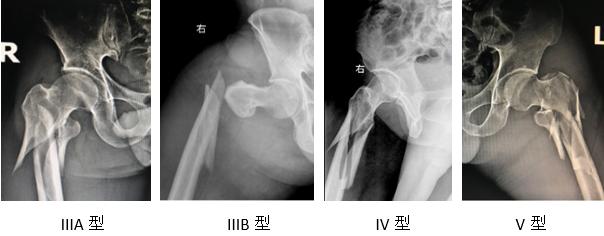

临床常用的有AO分型,Russell-Taylor分型以及Seinsheimer分型,我们习惯使用Seinsheimer分型。

Ⅰ型股骨转子下骨折需要CT才能明确诊断,往往见于长期应用阿仑膦酸盐药物患者。骨折越简单,往往闭合复位越困难,我们的技巧是麻醉后将患者置于牵引床,开始并不牵引,先对骨折做一定位,其外侧做一切口,用钢丝环扎(并不拧紧)骨折远近端进行初步辅助复位,然后进行牵引,并内旋或外旋骨折远端(以子求母)进行复位,骨折复位良好后,再插入髓内钉的导针、扩髓等操作。股骨转子下骨折血运较差,愈合时间长,微创复位技术,可减少骨折端血运的破坏是骨折愈合的良好条件。